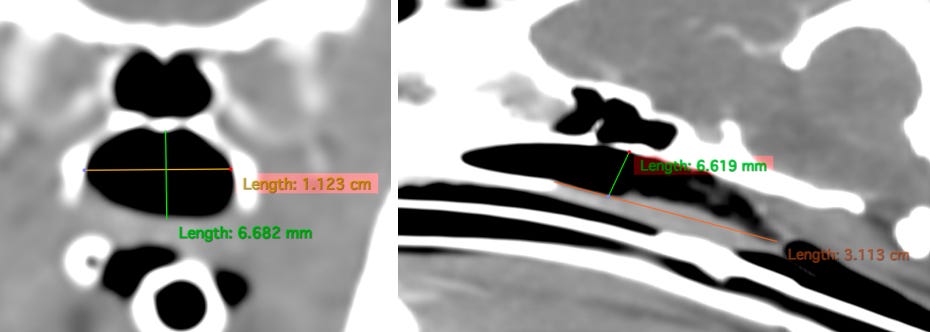

Realizamos imagen avanzada del cráneo, donde podemos observar en el aspecto caudal de la nasofaringe una estenosis grave con pérdida casi completa de la luz (flechas verdes).

Oralmente a esta estenosis se observa leve aumento de espesor del paladar blando, además hay acúmulo de material hipoatenuante sin realce aparente mezclado con burbujas de gas (flechas amarillas).

La altura de la nasofaringe previo a la estenosis es de 6,6 mm, el ancho 1,1 cm. La distancia entre el paladar duro y la estenosis es de 3 cm.